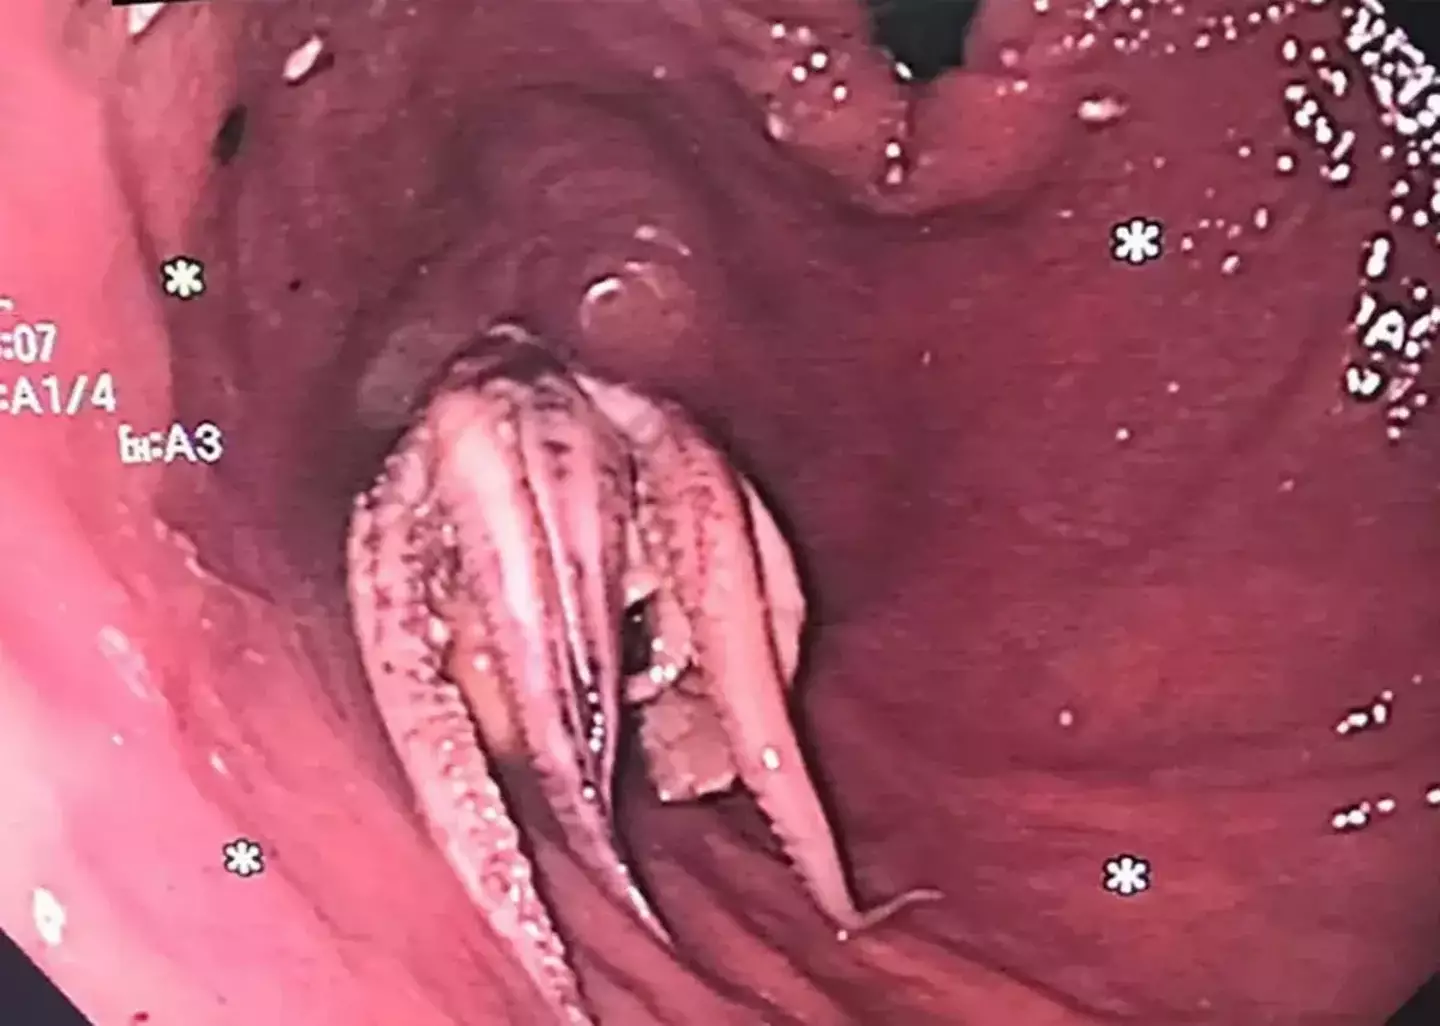

After the scan revealed a hyperdense mass in the man’s oesophagus, the 55-year-old was then ordered to have an oesophagogastroduodenoscopy.

EGD for short, it's a simple procedure to examine the lining of the esophagus, stomach, and first part of the small intestine.

Although attempts to remove the creature were unsuccessful the first time round, doctors were eventually able to extract it.

The medical team explained: “The ‘push technique’ is the primary method recommended with high success rates, however applying excessive force can cause oesophageal perforation.”